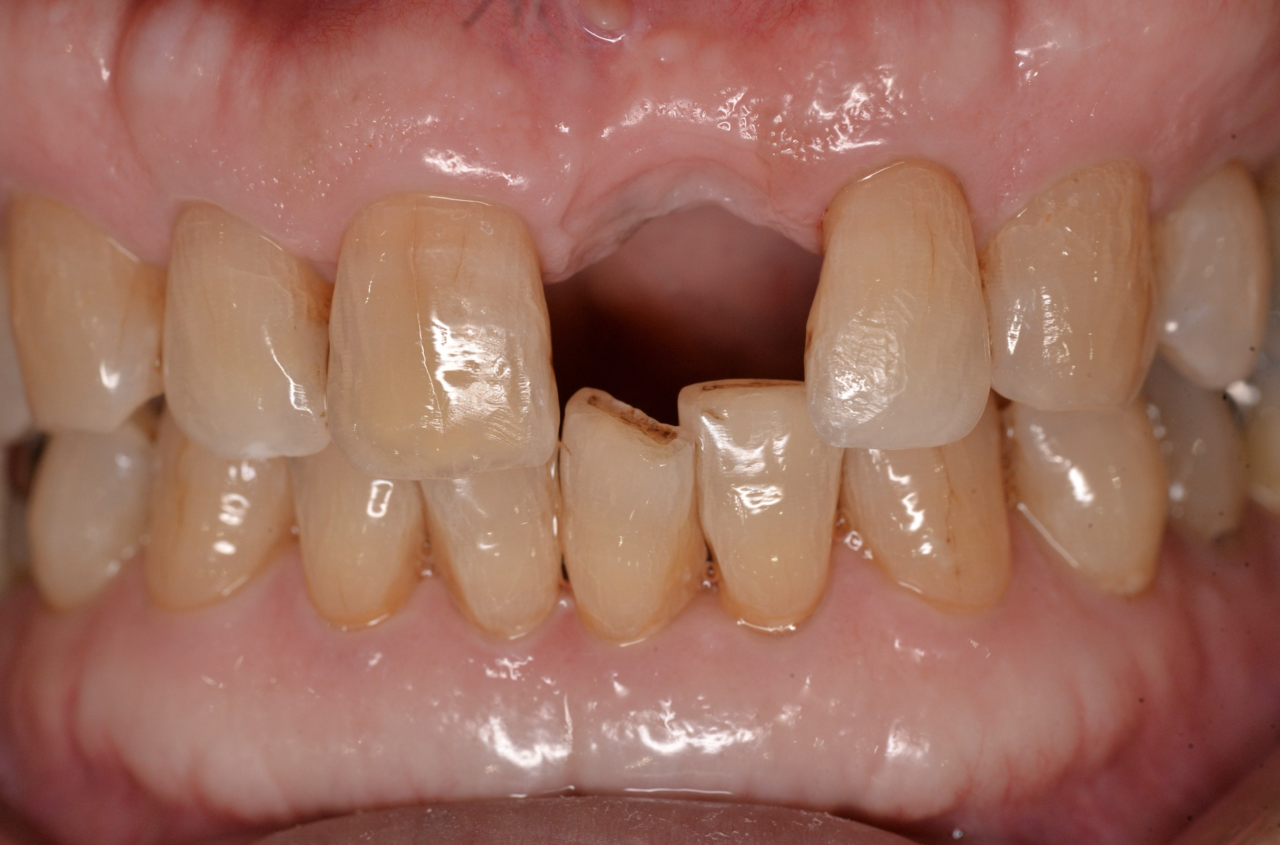

Before

60代男性 失った前歯をインプラントで復元

治療期間:1年半* 費用:約65万円

デメリット:費用が高額 外科処置が必要

After

根尖病変にて抜歯した部分にインプラントを埋入

薄くなった骨補う処置(GBR)を行いました

*骨の安定に時間を要し通常より期間がかかりました